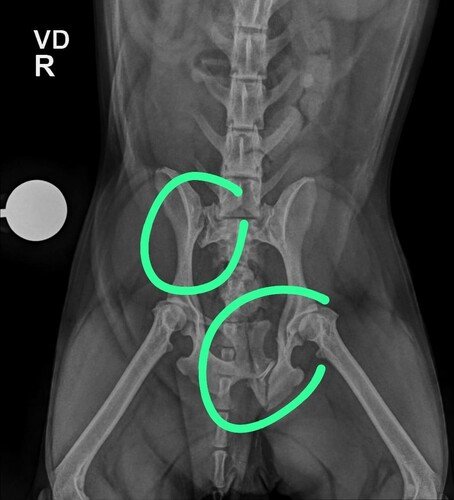

A Babalu sofreu uma lesão na coluna e na pelve e está sem movimentos nas patinhas inferiores, por isso ela fez uma uma operação de emergência e vai precisar também de cuidados pós operatórios como remédios e cuidados especiais. Além dessa cirurgia o médico identificou que ela está com uma lesão no ligamento de um dos joelhos e depois vai precisar de mais uma operação. Vamos ajudar a Babalu e trazer a alegria dela de volta? ❤️